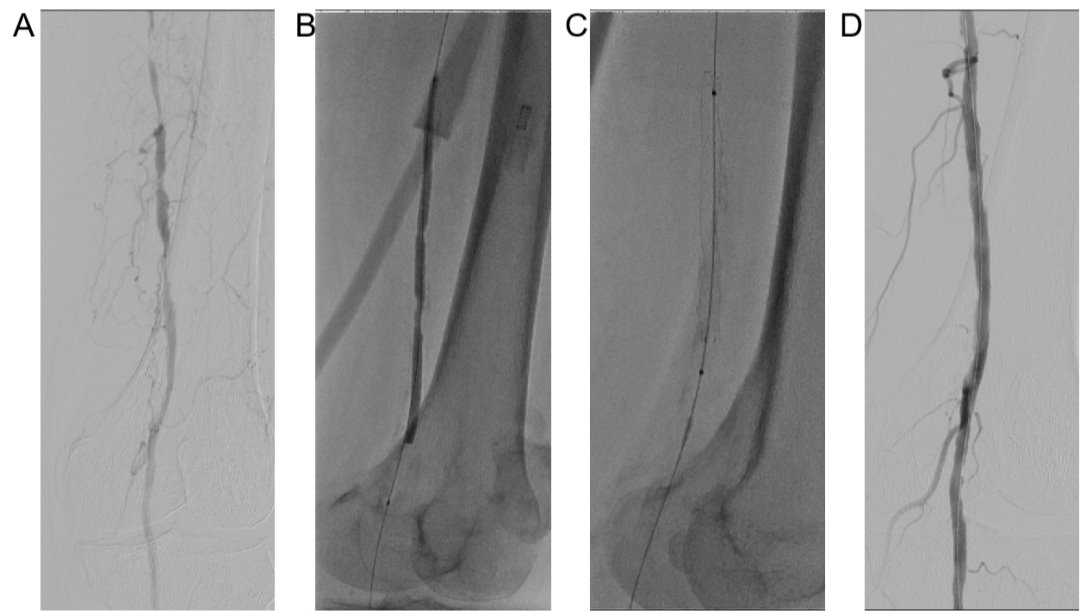

【医路速览·新闻】第101期:我院普通外科-血管外科组成功介入下开通一例下肢动脉闭塞